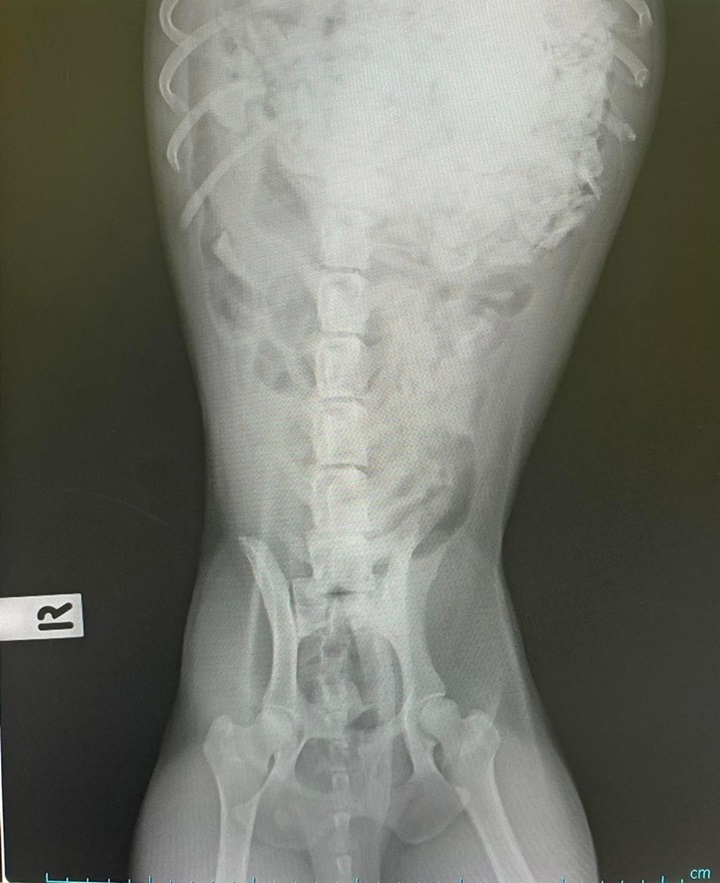

เป็นอุทาหรณ์สำหรับผู้เลี้ยงสุนัขทั้งหลาย ที่ยังมีความเข้าใจผิด ๆ ว่าสุนัขกับกระดูกเป็นของคู่กัน ซึ่งในความเป็นจริงแล้วเป็นสิ่งที่ไม่ถูกต้องนัก และอาจเป็นอันตรายต่อสุนัขได้ โดยล่าสุด (20 มีนาคม 2565) เฟซบุ๊ก โรงพยาบาลสัตว์ศรีวรา โคราช ได้เผยภาพของสุนัขตัวหนึ่ง ที่ถูกนำส่งโรงพยาบาลหลังเกิดอาการผิดปกติ จากการกินกระดูกเข้าไป จนกลายเป็นสิ่งแปลกปลอมในกระเพาะอาหาร

โดยระบุว่า "ภาพชินตาว่าสุนัขกับกระดูกเป็นของคู่กัน อาจจะไม่ใช่สิ่งที่ถูกต้องนัก เพราะไม่ว่าจะเป็นกระดูกของสัตว์ชนิดไหน หากแตกเป็นชิ้นเล็ก หรือเป็นเศษที่มีความแหลมคมก็สามารถเป็นอันตรายต่อน้องหมาได้เช่นกันนะคะ บางตัวโชคร้าย กระดูกที่ทานเข้าไปทำให้เกิดการอุดตันทางเดินอาหาร ทำให้สุนัขอาเจียน ปวดท้อง ถ่ายไม่ออกรึถ่ายมีเลือดปน ควรรีบพาพบคุณหมอทันทีค่ะ"